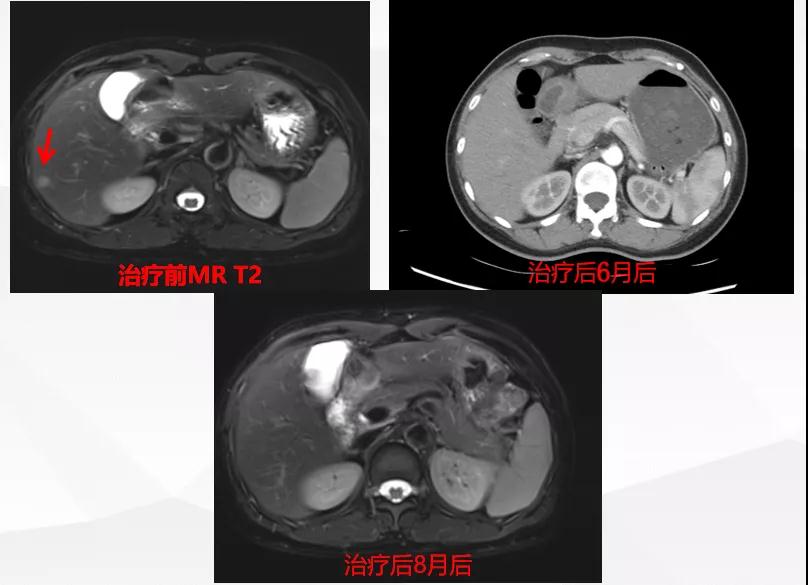

曲妥珠单抗辅助治疗结束6个月后,患者出现左侧胸部疼痛,ECT检查提示:左侧第4、5肋骨及T2胸椎转移;MR提示:T2椎体转移,肝S6段异常强化灶,考虑转移瘤可能性大;脑转移(图1)。

图1